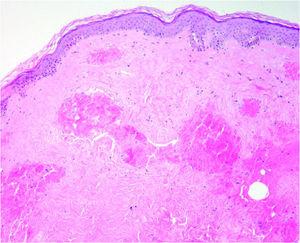

Una biopsia de una zona afectada mostró ectasia del plexo vascular superficial, melanófagos salpicados y fibroblastos estrellados. La epidermis no mostraba alteraciones (fig. 2).

Fig. 2.--El estudio histológico de la zona poiquilodérmica mostraba ectasia del plexo vascular superficial. (Hematoxilina-eosina, ×20.)

Nuestra paciente recibió tratamiento con el LCP, Candela corp. de 595 nm utilizando pulsos ultralargos de 3 ms. Tuvimos la oportunidad de realizar estudios histológicos que se correlacionaban con la clínica y con el modo de acción del LCP. Las telangiectasias son vasos dilatados, tal y como encontramos en la biopsia pretratamiento. La presencia de fibroblastos de morfología estrellada es típica de la piel radiada. Inmediatamente después del tratamiento con LCP aparece la púrpura. En una biopsia realizada en ese momento encontramos congestión vascular sin daño epidérmico. Los pulsos de alta energía, como los utilizados con el LCP, producen coagulación intravascular sin daño perivascular 2. La epidermis está respetada y los vasos superficiales de la dermis papilar y reticular contienen eritrocitos aglutinados, fibrina y trombos plaquetarios 2, tal y como se vio en nuestro caso. En la biopsia que se tomó un mes después del tratamiento no se observaron vasos anómalos ni cicatrices, ya que los vasos tratados con el LCP son destruidos y reemplazados lentamente por vasos normales 2. Clínicamente logramos un resultado muy satisfactorio en 5 sesiones sin efectos secundarios. El tratamiento fue bien tolerado y la paciente quedó contenta con el resultado.